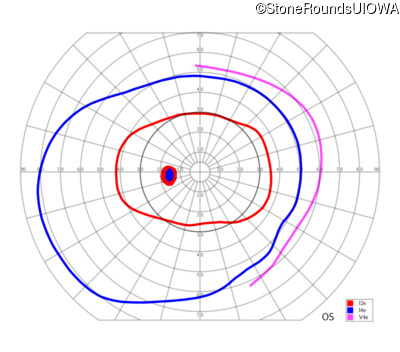

| OD | OS | ||

|---|---|---|---|